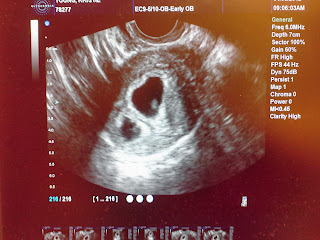

Two heartbeats beating great!!! Baby A is in front of Baby B. Baby A measured 6w1d and 129hr and Baby B measured 6w2d and 120hr. We go back on the 16th to see out little babies growing. I cannot even put into words how blessed I feel and also how overwhelmed. Its hard to go from trying so hard to get pregnant to actually being pregnant. Im just so thankful!!! Cant wait to see my little babies again :)